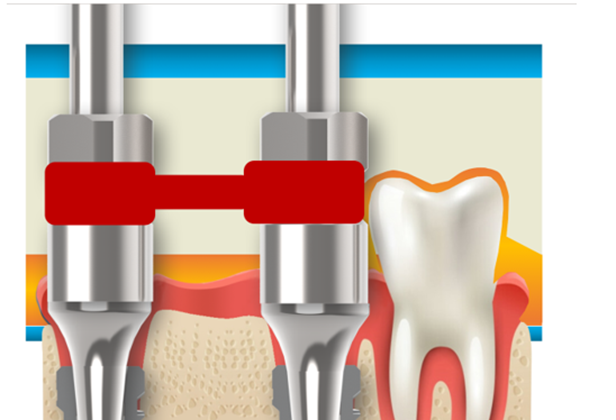

O componente Mini Cônico é indicado para casos múltiplos, próteses fixas e protocolos em geral (dois ou mais elementos sobre implantes).

1) confeccionar a prótese diretamente sobre o componente, onde a zircônia será parafusada na “cabeça do componente”;

2) confeccionar a prótese sobre um “link” metálico (Base T), elaborado e desenhado para ser utilizado sobre o Mini Cônico.